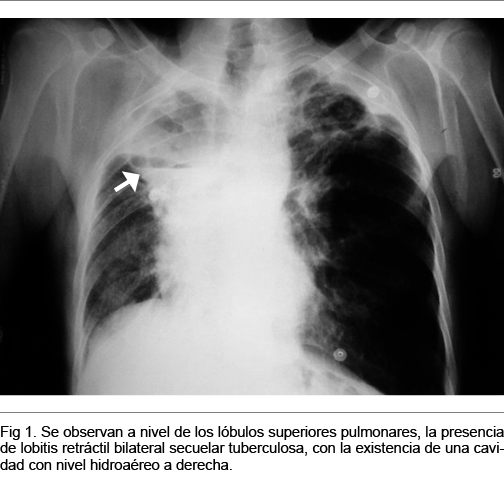

Rx de tórax (Figura 1): importantes elementos secuelares fibro-retráctiles bilaterales a predominio biapical, con cavidades biapicales con nivel hidroaéreo a derecha.